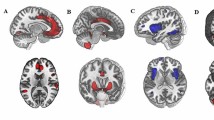

Positive connectivity

The majority of findings demonstrated positive connectivity between regions, with 183 pairings; see Table 2 for a full list of pairings and Fig. 2 for a visual representation of the most consistent findings. Compared to controls, those with SAD had higher connectivity between the following regions: frontal–amygdala (5 studies; 15 pairings), temporal–amygdala (4 studies; 6 pairings), and frontal–parietal (3 studies; 4 pairings). Compared to controls, those with SAD had lower connectivity between the following regions: frontal–amygdala (4 studies; 7 pairings), frontal–parietal (4 studies; 18 pairings), temporal–temporal (2 studies; 11 pairings), and frontal–temporal (2 studies; 13 pairings).

This systematic review aimed to obtain a comprehensive understanding of the brain regions and networks implicated in people with SAD compared to controls, focusing on resting-state multimodal neuroimaging techniques and analysis methods. It included the examination of associations between brain and dimensional measures in people with SAD. Of the 35 studies, the most common analysis approach involved seed-based analysis. Frontal regions were most implicated across studies and analysis methods and in the relationships between brain and dimensional measures. Even when excluding findings from studies that had smaller sample sizes that were uncorrected [21, 23, 40, 41], similar findings remained. From seed-based studies, the SAD group had both higher and lower positive connectivity between the amygdala and frontal regions and between the amygdala and parietal regions, and lower positive connectivity between the amygdala and temporal regions. Findings from ALFF predominantly demonstrated lower ALFF across 17 frontal regions in those with SAD compared to controls. Likewise, across other non-seed analysis methods (e.g., graph theory, MVPA), frontal regions (i.e., superior and middle frontal gyrus) were most reported throughout. The superior frontal gyrus was most commonly implicated across all fMRI studies, being reported 63 times. It was also most consistently found to be associated with social anxiety symptoms, with results showing negative and positive correlations. The middle frontal gyrus, inferior frontal gyrus, and anterior cingulate cortex were also frequently reported across studies. Other frontal regions implicated, albeit to a lesser extent, were the dorsolateral PFC, the dorsomedial PFC, the precentral gyrus, Rolandic operculum, rectal gyrus, supplementary motor area, and the orbitofrontal gyrus.

Parietal–frontal connectivity

Eighteen pairings across four studies found evidence of lower connectivity and four pairings across three studies found evidence of higher connectivity between parietal and frontal regions in those with SAD compared to controls. The most commonly reported pairings were lower connectivity between the bilateral posterior cingulate gyrus and the bilateral superior frontal gyrus, the bilateral precuneus and the right superior frontal gyrus, and the bilateral precuneus and the bilateral gyrus rectus.

Amygdala–temporal connectivity

Six pairings across four studies found higher connectivity between these regions in those with SAD compared to controls, and only one pairing from a separate study demonstrating evidence of lower connectivity. The most commonly reported pairings were between the left amygdala and the bilateral fusiform gyrus, and the bilateral amygdala and the bilateral parahippocampal gyrus.